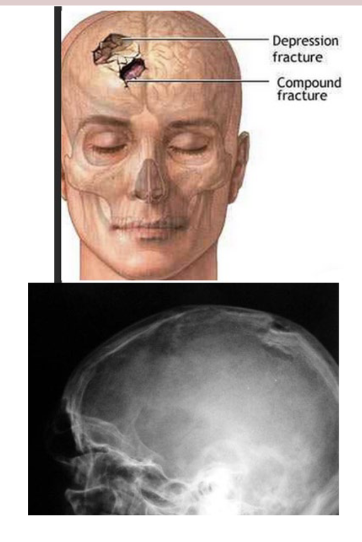

What fracture is this?

Depressed (Ping-pong)

Describe a depressed (ping-pong) fracture?

Skull fx where the fragment is depressed in like a ping pong ball